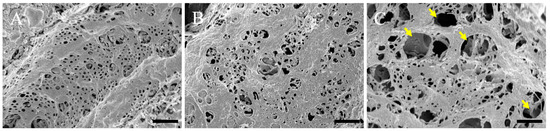

2.2. Histopathological Evaluation of the Hepatic Structural Changes in Response to Hepatic Encephalopathy